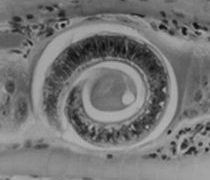

線虫類 トリヒナ症または旋毛虫症(症状・予防) ~ 重度感染では症状は明瞭であり、疾病経過を3期に分けることができる 自然感染では多くの感染例が軽度であり、無症状に経過します。重度感染では症状は明瞭であり、疾病経過を次の3期に分けることができます。●腸寄生期トリヒナ寄生肉を与えると翌日から1週間にかけて軽度な発熱、食欲不振、悪心、嘔吐、軽度の腹痛、下痢が観... 2021.10.23 線虫類